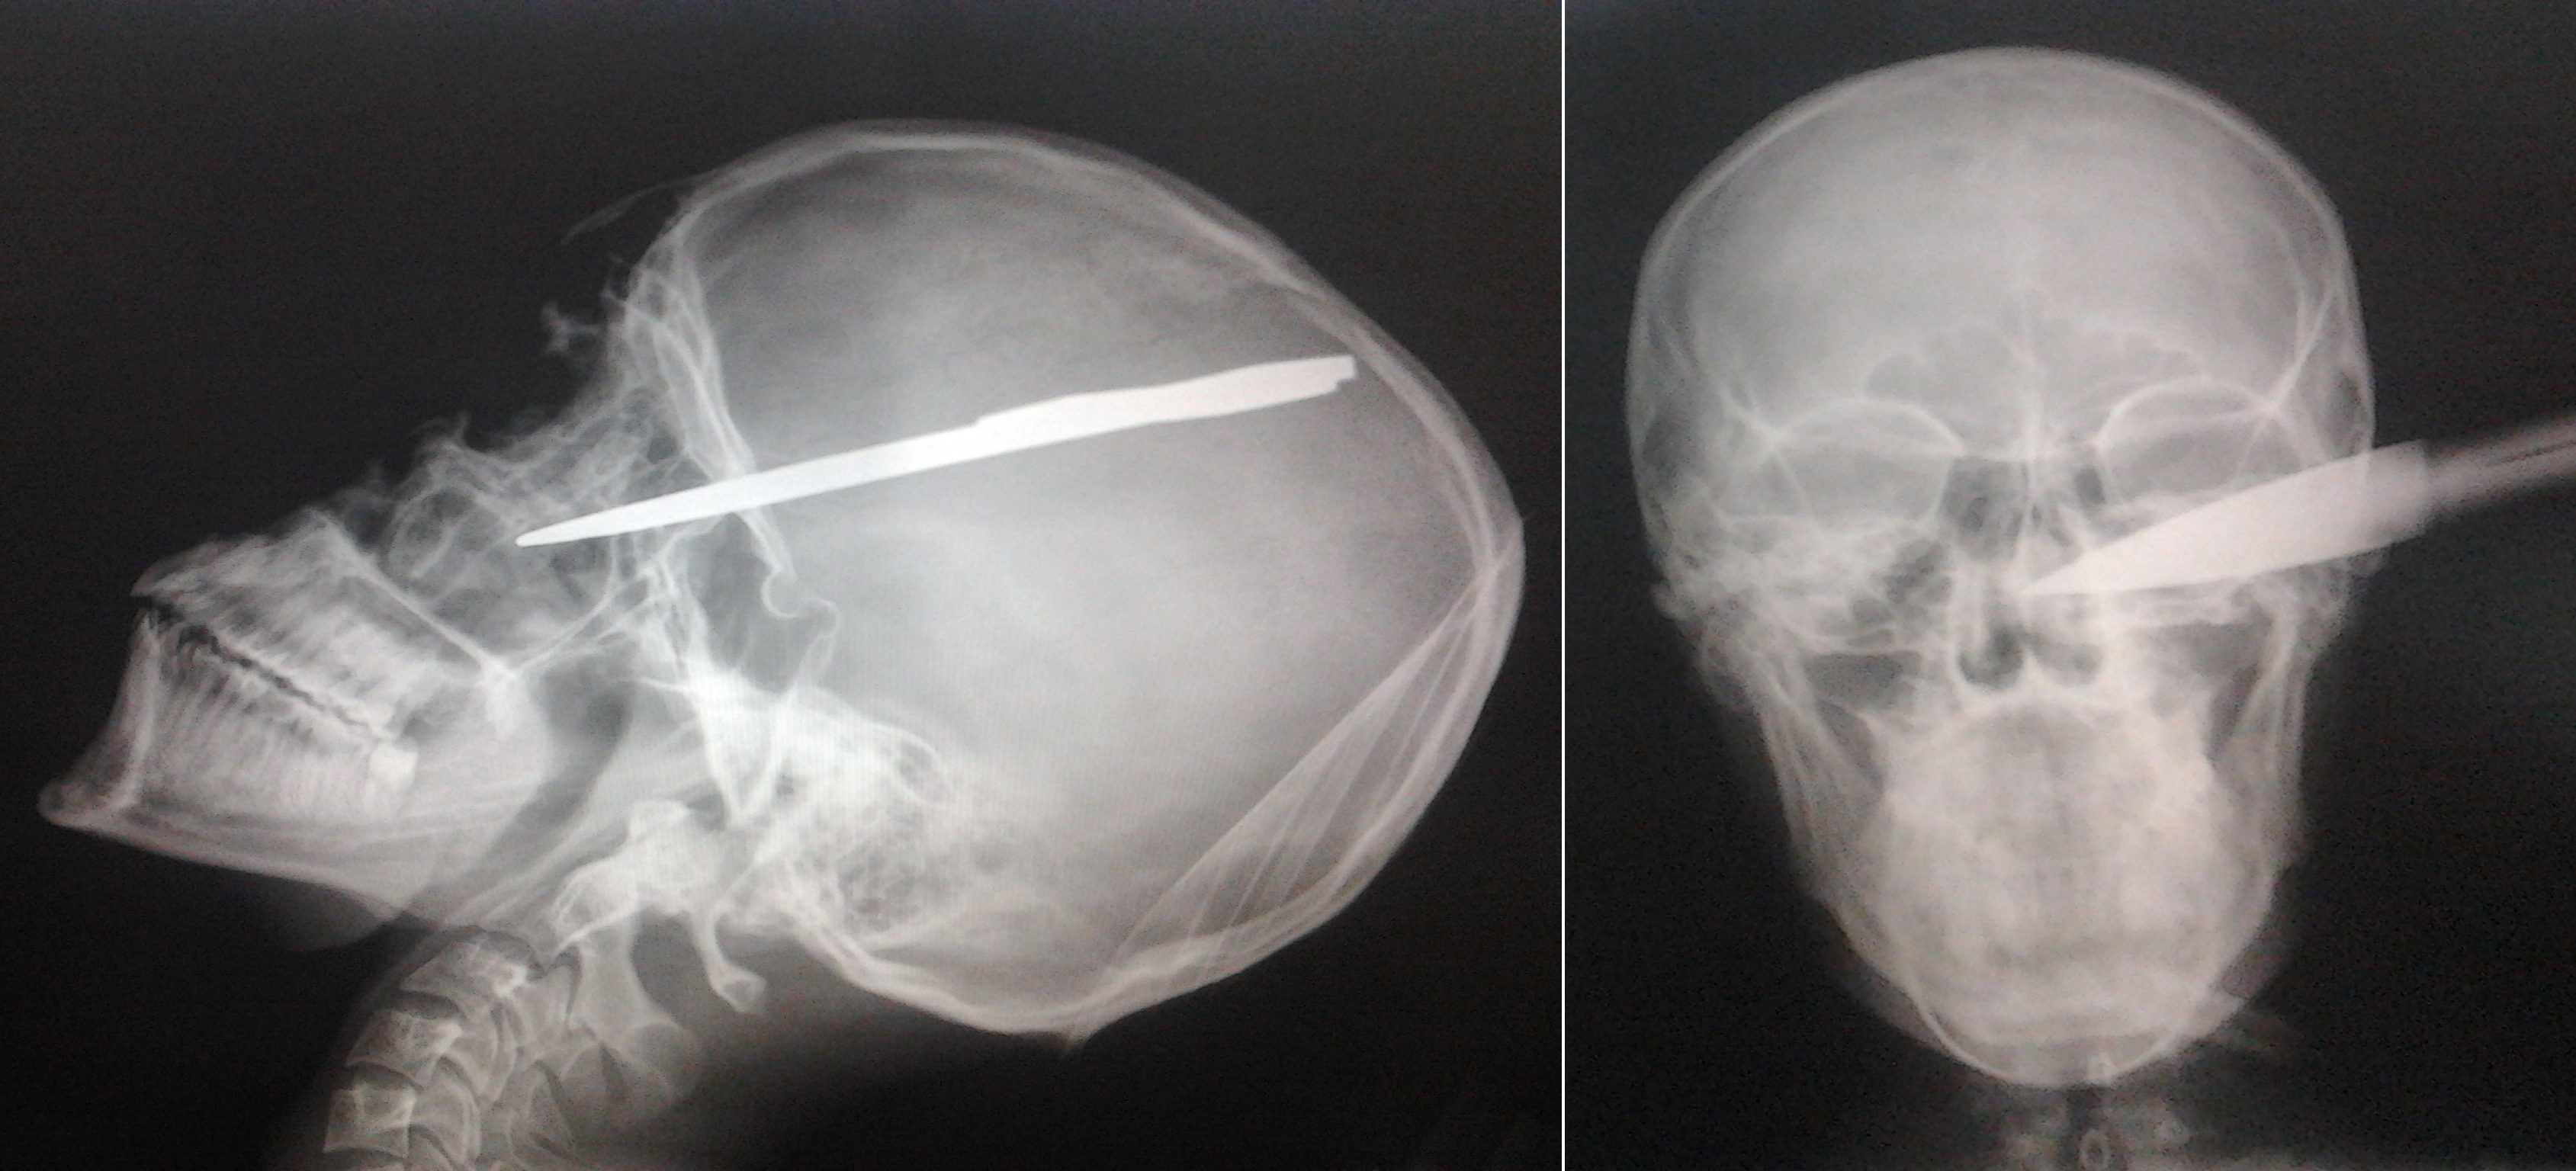

Un tanar de 20 de ani a uimit medicii! Barbatul a ajuns la spital cu o sabie efectiv infipta in cap! Dupa o operatie care a durat 45 de minute, verdictul a fost incredibil: leziunile au fost minore, iar in patru zile omul a plecat acasa!

I.A.G. (20 de ani) a fost externat din spital dupa patru zile si va ramane, cel mai probabil, in istorie drept barbatul care a trait dupa ce o sabie i-a fost infipta in cap. In ciuda faptului ca lama armei i-a patruns in craniu aproximativ sase centimetri, nici un element vascular nu a fost atins, au sustinut surse medicale.

Scandalul s-a petrecut noaptea, iar unul dintre inculpati a lovit victima cu intentia de a o omori. Cert este ca planurile le-au fost date peste cap de …destin! Barbatul care parea sa nu aiba nicio sansa de supravietuire, a scapat aproape nevatamat si dupa patru zile a fost externat. Radiografia e socanta si arata cat de aproape a fost, de fapt, tanarul de moarte si ce miracol e ca a supravietuit. (A.S.)